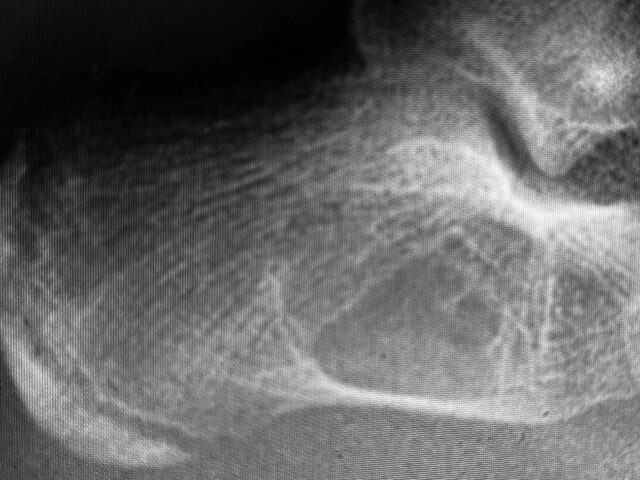

Απλή Οστική Κύστη (UBC): Σύγχρονη Ορθοπαιδική Προσέγγιση σε Παιδιά & Εφήβους Η διάγνωση μιας οστικής βλάβης στο παιδί προκαλεί εύλογα ανησυχία στους γονείς. Ωστόσο, η Unicameral Bone Cyst (UBC), γνωστή στα ελληνικά ως απλή οστική κύστη, αποτελεί μία από τις πιο συχνές και καλοήθεις οντότητες στην παιδοορθοπαιδική. Τι είναι η Απλή Οστική Κύστη; Η απλή…